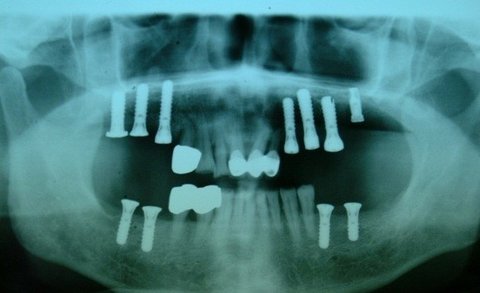

‘임플란트’는 환자들의 만족도가 높은 치과치료법이다. 그러나 ‘반영구적‘ 이라고 알려진 임플란트도 시술 후 제대로 관리를 하지 않으면 잇몸병이 생기거나 임플란트 자체에 구조적인 변형이 생기는 등 여러 문제가 생길 수 있다. 임플란트 시술 후, 당신은 몇 번이나 치과를 찾았는가?

임플란트는 더 이상 낯선 시술이 아니다. 주변을 돌아봐도 꽤 많은 사람이 이 인공치아를 심은 채 살아간다는 것을 알 수 있다. 그런데 사람들이 임플란트에 대해 오해하고 있는 것이 하나 있다. 바로 ‘반영구적’이라는 믿음이다.

임프란트가 반영구적일 수 있다는 기대는, 1964년 스웨덴에서 처음 개발되어 시술된 ‘브레네막(개발자의 이름)’ 임플란트가 1990년대까지도 유지되었다는 사례가 보고 되면서 시작 되었다. 임플란트가 시술 후 30년 가까이 잘 유지되었다면 확실히 반영구적이라고 말할 수 있을 것이다. 하지만 그것은 ‘잘 관리되었을 때’의 이야기다. 전문의들은, 임플란트는 결코 반영구적인 치료법이 아니며 오히려 시술 후에 더 철저한 관리가 필요하다고 말한다.

자연치에는 세균에 대한 방어기전이 있지만, 임플란트는 그렇지 않다고 한다. 양치질을 잘 하지 않아 치석이 끼게 되면 잇몸병이 생기는데, 이럴 때 임플란트는 자연치에 비해 더 취약하다고 한다.

*식립된 나사 언제든 풀릴 수 있어

자연치의 경우 대체로 표면이 매끄럽기 때문에 양치질을 잘하면 치태가 제거되고 그에 따라 치석이 형성되는 일도 막을 수 있다. 그러나 임플란트는 턱뼈에 나사를 박아 넣은 다음 그 위에 인공치아를 끼우는 방식으로, 나사의 요철 부분에 이물질을 들러붙기 쉬운 구조이며, 이 경우 양치질로는 치태, 치석을 제거하기가 어렵다. 세균덩어리인 치석이 이렇게 임플란트에 들러붙기 시작하면 우리의 인체는 방어기전이 작동하여 세균에서 멀어지기 위해 뼈가 조금씩 가라 앉게 된다. 즉 임플란트가 식랍된 턱뼈가 임플란트를 타고 내려온 세균 때문에 점점 없어진다는 뜻이다. 이 과정이 오래 반복되면 결국 임플란트가 구조적으로 취약해질 수밖에 없다. 한편 임플란트는 기둥과 인공치아가 나사로 연결되는 방식이기 때문에 언제든 나사가 풀릴 수 있다는 점도 생각해야 하다. 나사가 허걸워진 상태에서 딱딱한 음식이라도 먹게 되면 부러질 수도 있다. 임플란트에 쓰이는 나사 즉 ‘기둥’은 강도가 높다. 하지만 실제 폭은 1.5mm 정도에 불과하다. 굉장히 가늘다. 꽉 조였다고 해도 사람의 씹는 힘이 사실은 무시무시하기 때문에 관리가 제대로 되지 않은 상태에서 과도한 힘이 가해지면 부러질 수도 있다.